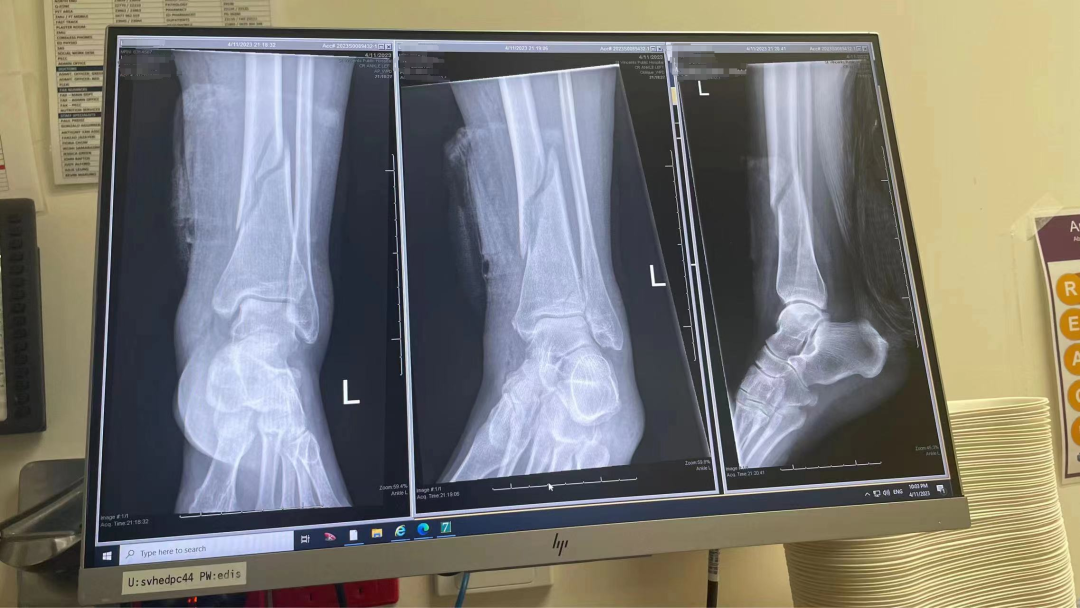

L女士从出租车上摔下后,因左腿疼痛来到 SVH 急诊室。经检查发现其左侧胫骨轴骨折(G1关节内开放性骨折),于 11月5日接受了左胫骨切开复位内固定手术治疗,无并发症。